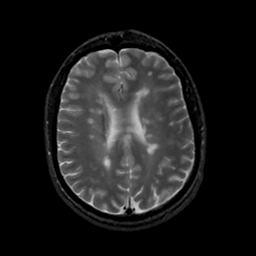

MR Study #18, July 21, 1991 -- Slice #32